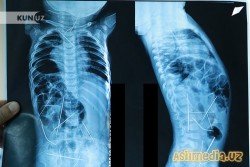

Рентген суратларида аён бўлдики, чақалоқнинг танасида 16 дона (!) игна бор ва улар энг камида икки ойдан буён болани қийнаб келади. Шундай қилиб, бола ва унинг онаси зудлик билан Тошкентга юборилди. Республика шошилинч тиббий ёрдам илмий марказига келтирилган бола тезкорлик билан жарроҳлик столига ётқизилди.

Марказдаги Болалар жарроҳлик бўлими мудири, профессор Акиловнинг таъкидлашича, барча игналар танада турлича жойлашган: уларни чақалоқнинг йўғон ичак қисмида, сийдик қопи, кўкрак қафасида, боланинг бўйин қисмида, умуртқа поғонасида, юрак остида аниқлашган.